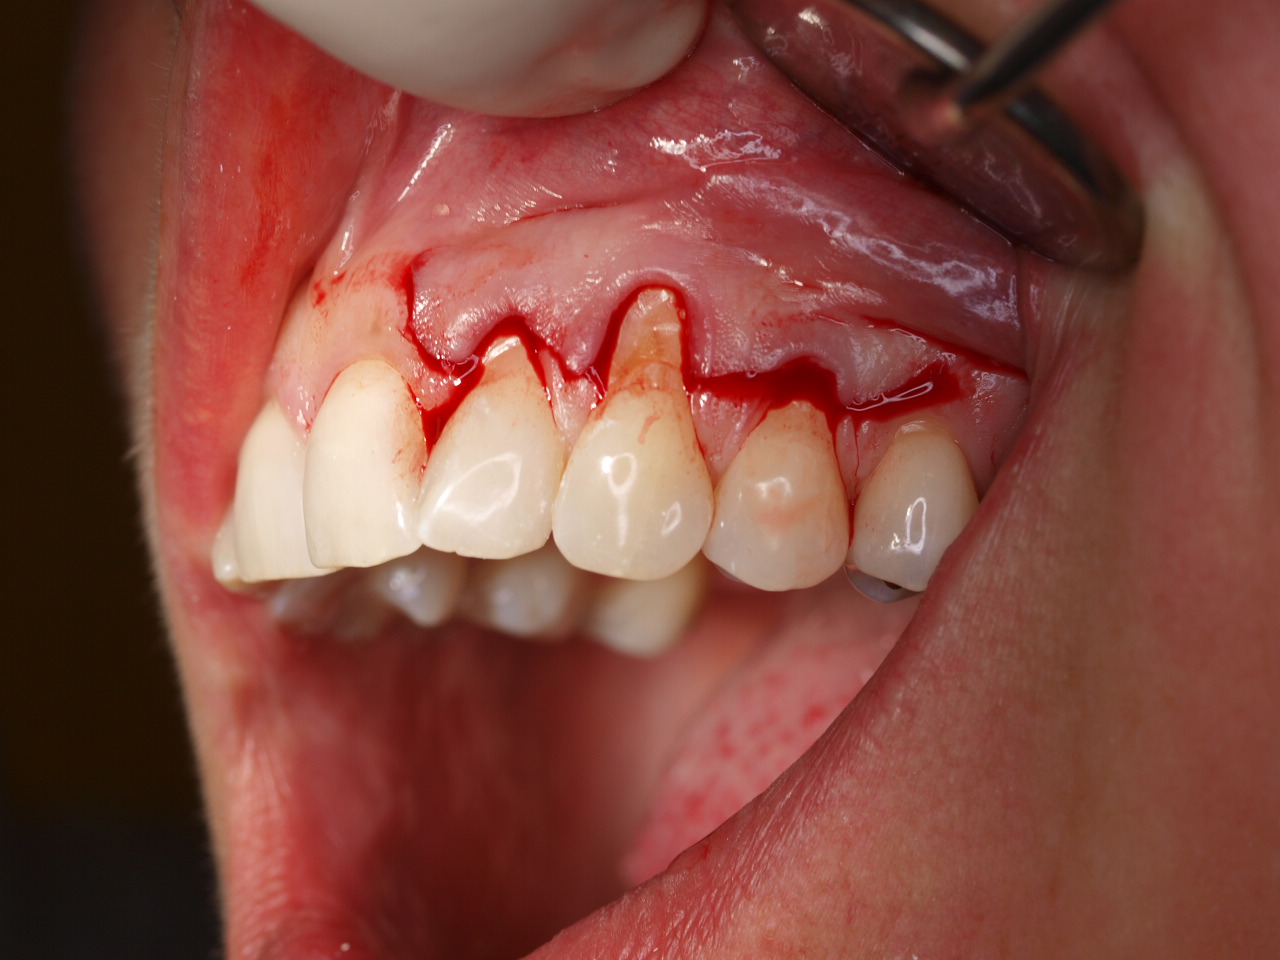

Multiple gingival recessions treated by MCAT with mucoderm® and Straumann® Emdogain® (2) - Rathe

Pre-operative clinical situation. Shallow multiple adjacent gingival recessions in the first quadrant.